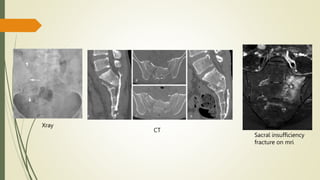

Imaging

๏‚ท Radiographs show only 30% of fractures

๏‚ท CT is diagnostic study of choice

๏‚ท MRI for suspected neural compromise

Xray

CT

Sacral insufficiency

fracture on mri